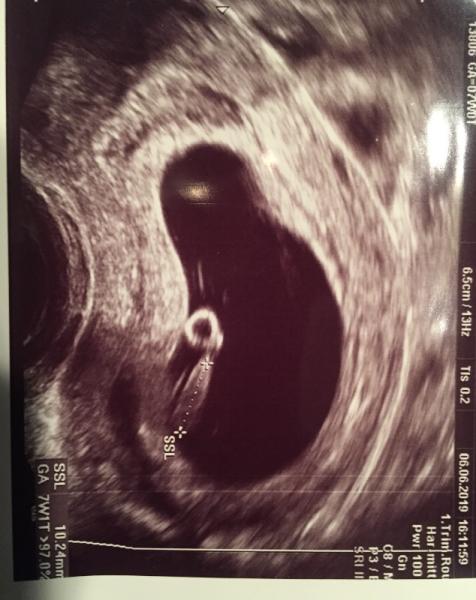

Juhuu wir hatten vorhin auch unseren 2. Termin. Ich bin lt. Frauenarzt jetzt 7+1,es ist 10,24mm groß und wir konnten das kleine Herzchen schlagen sehen. Mein Mann war ganz gerührt und hatte Tränen in den Augen. Es war super schön und wir freuen uns auf den nächsten Termin in 2 Wochen. Lg Mücke

Bild zu 2. Termin und Herzschlag - Forum für Januar - Mamis